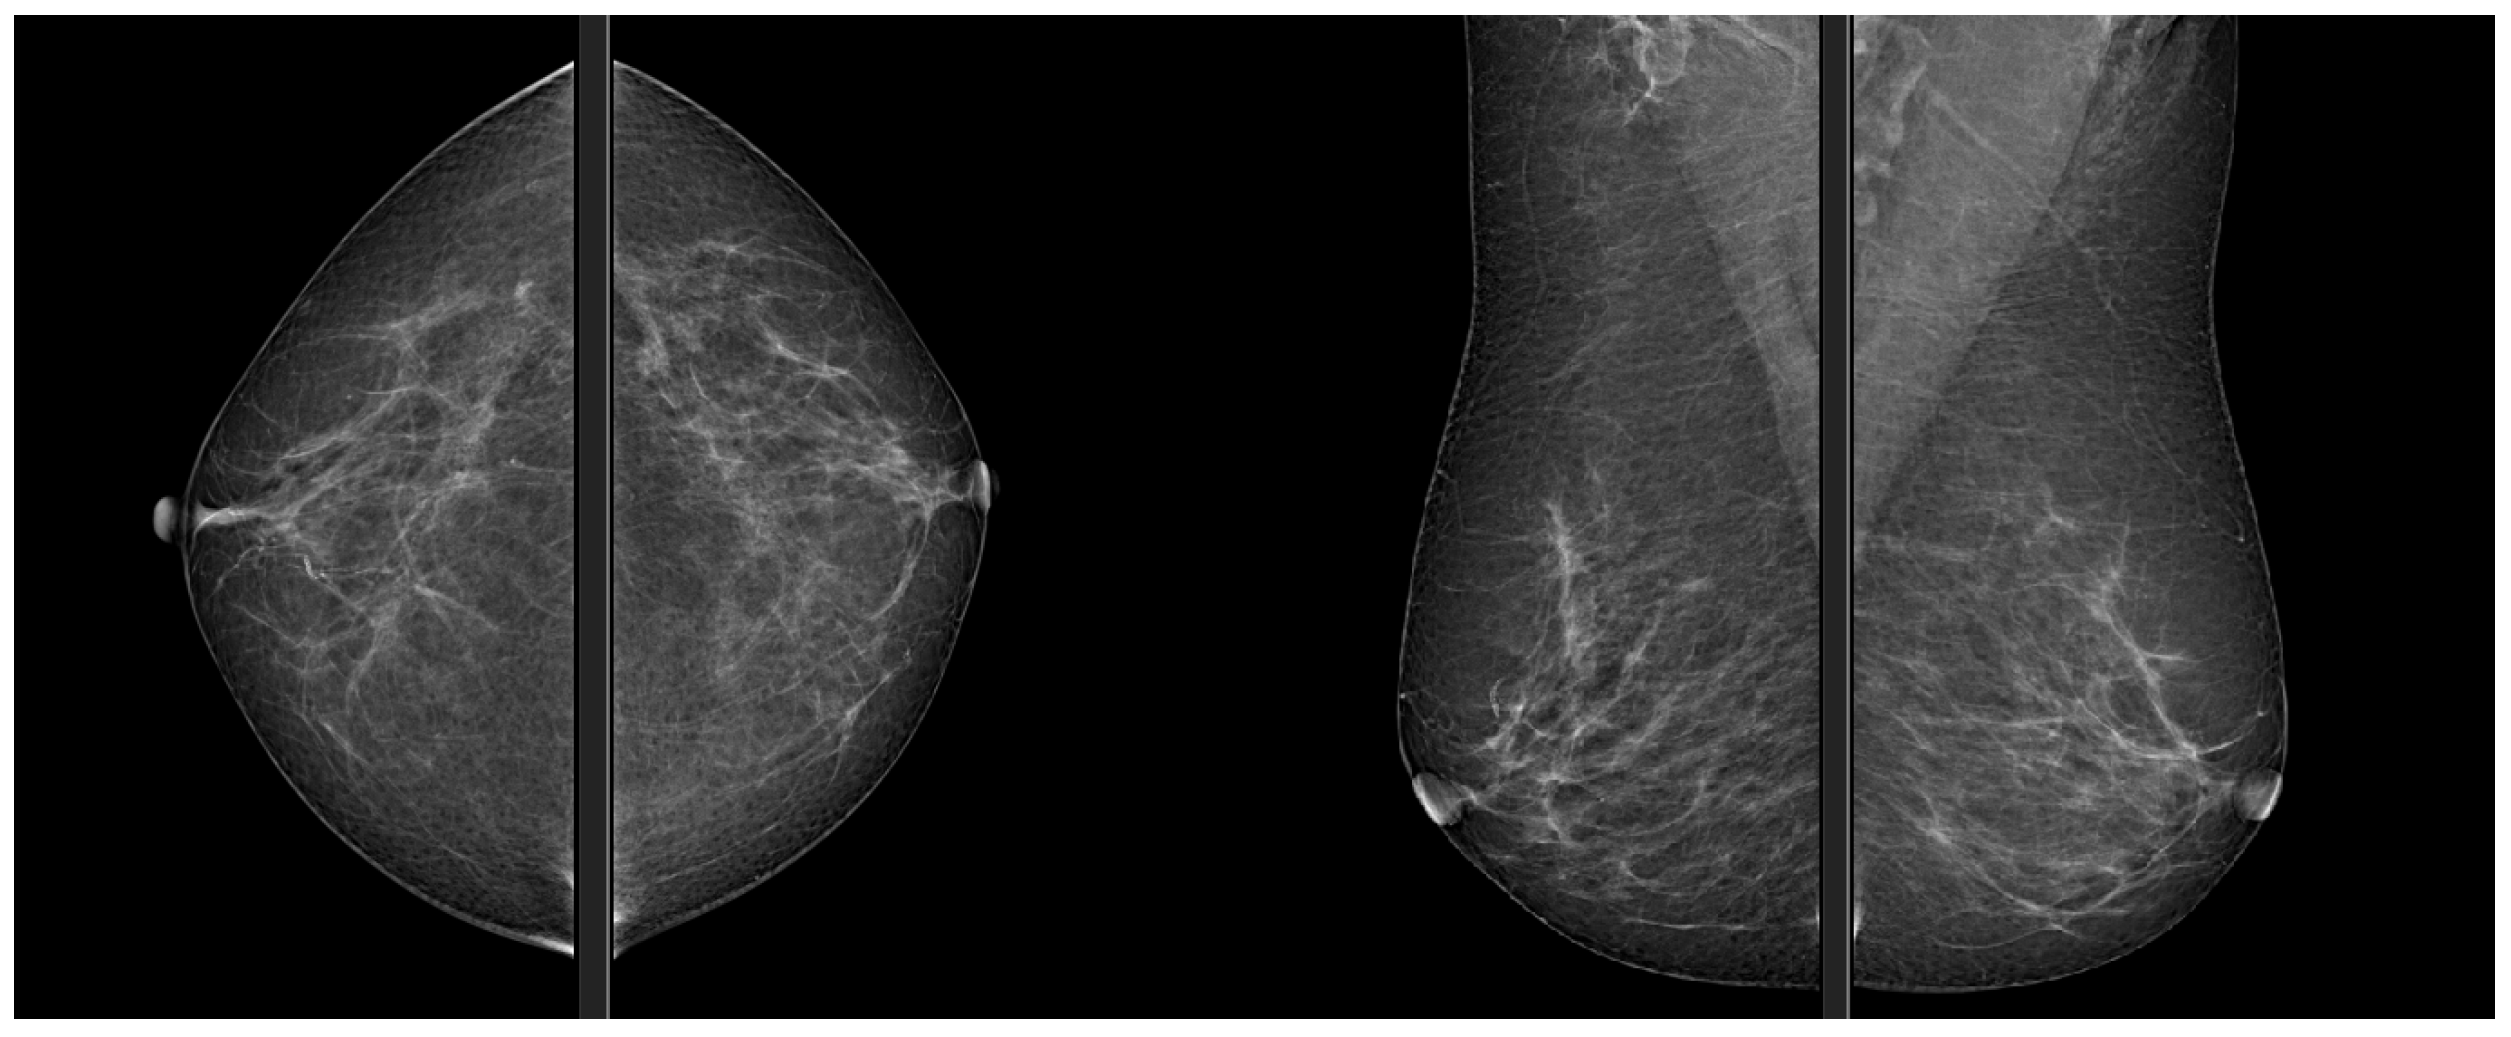

Mammography is the reference technique in breast cancer radiological diagnosis, and it is recognized as the main screening tool for its effectiveness, Figure 1. Its diagnostic efficacy is clearly superior to clinical examination, allowing the identification of small anomalies, especially in recognizing microcalcifications [1]. According to the directives of the Ministry of Health, breast cancer screening is aimed at women between the ages of 50 and 69 and consists of performing a mammogram every 2 years.

Figure 1.

Mammography, CC and MLO views.